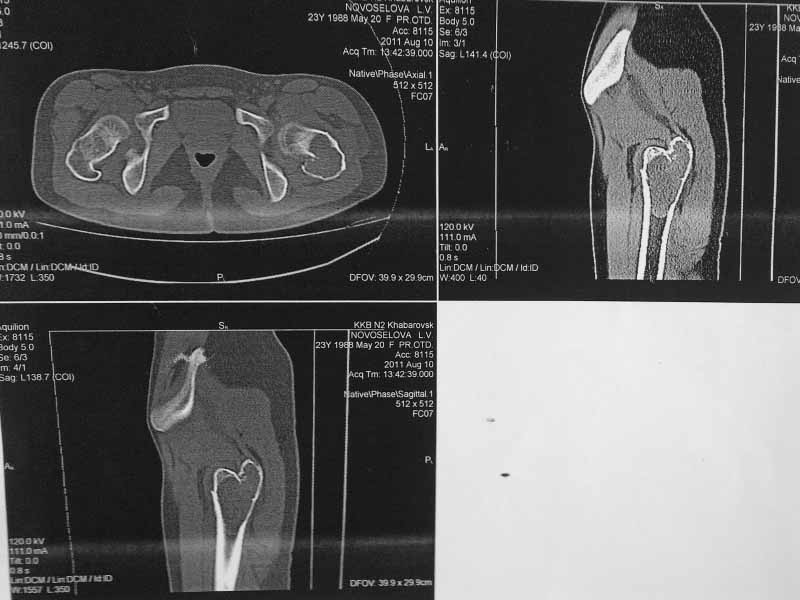

Молодая пациентка 23 лет. Травма в результате падения с высоты своего роста. Упала 2 дня назад доставлена к нам вот с такой картиной. Из анамнеза - боли беспокоят в течении полугода, постоянные. Никуда не обращалась. Уважаемое сообщество подскажите - ОБК?, Фиброзная дисплазия?, Киста?. Тактика ведения?. Девушка молодая!!!

На мой взгляд - это эссенциальная однокамерная киста или, скорее, аневризмальная.

А по пациентке:Обследования провели в легких чисто, лабораторно - без особенностей. Выполнили МРТ - костная киста, однокамерная. Оперирована - створчатая остеотомия, удаление кисты, костная пластика аутокостью с гребня подвздошной кости, остеосинтез DHS со сприральным клинком, створка фиксирована пластинами монокортикально.

Макроскопически - слизеподобное содержимое темно-бурого цвета, отдали на гистологию.